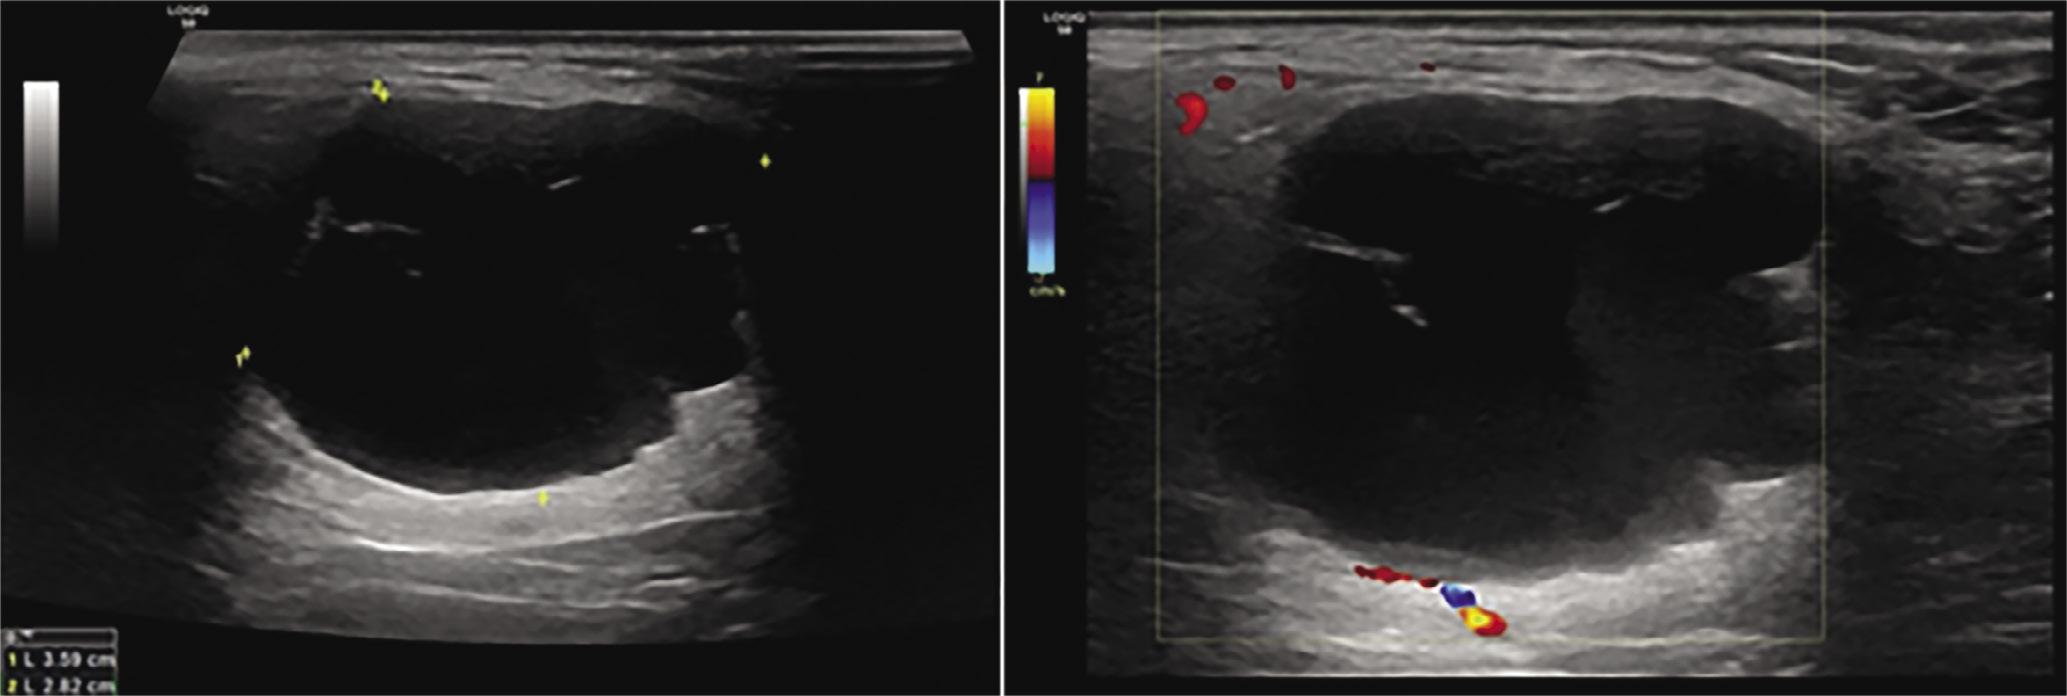

| 2nd cleft | 16 | 7/9 | Hypoechoic/hyperechoic (1 case)/mixed (1 case) | 1 (1 inconclusive)/14 |